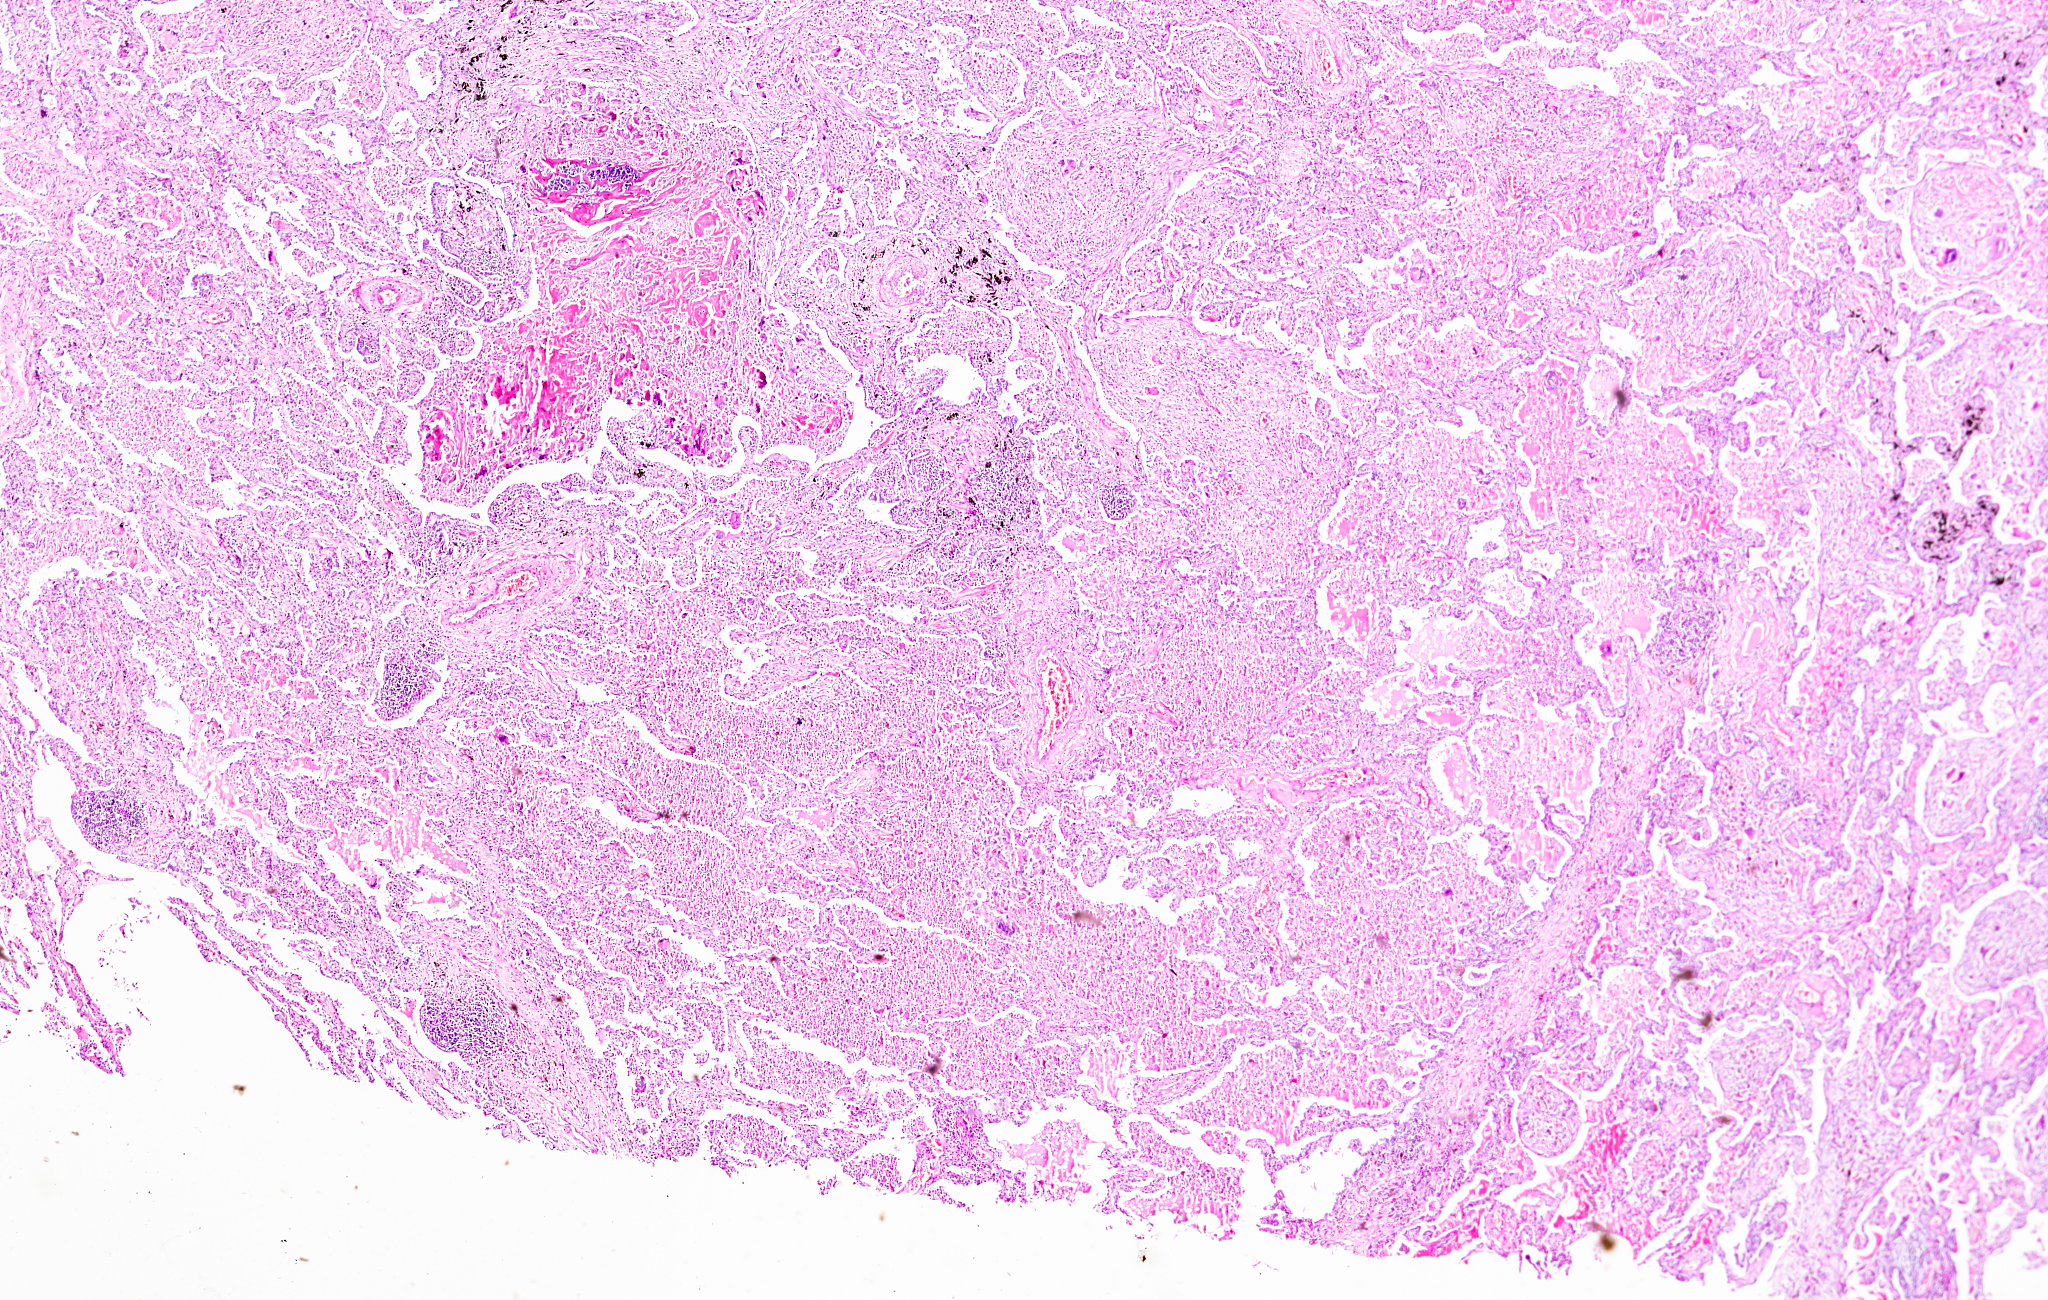

肉芽肿性炎症由上皮样组织细胞团块和多形性炎性浸润混合而成,有时伴有凝固性坏死。孤立存在的肉芽肿是一个非特异性的发现。然而,在临床病史的基础上,肉芽肿的存在可以帮助缩小鉴别诊断范围并指导进一步的检查。这种模式的典型关联是结核和结节病,但它们也可以在其他真菌感染或对外来物质或恶性肿瘤的反应中看到。清单:肉芽肿模式的病因学考虑。

翻译:Granulomatous inflammation consists of nodular aggregates of epithelioid histiocytes mixed with a polymorphous inflammatory infiltrate with or without coagulative necrosis In isolation granulomas are